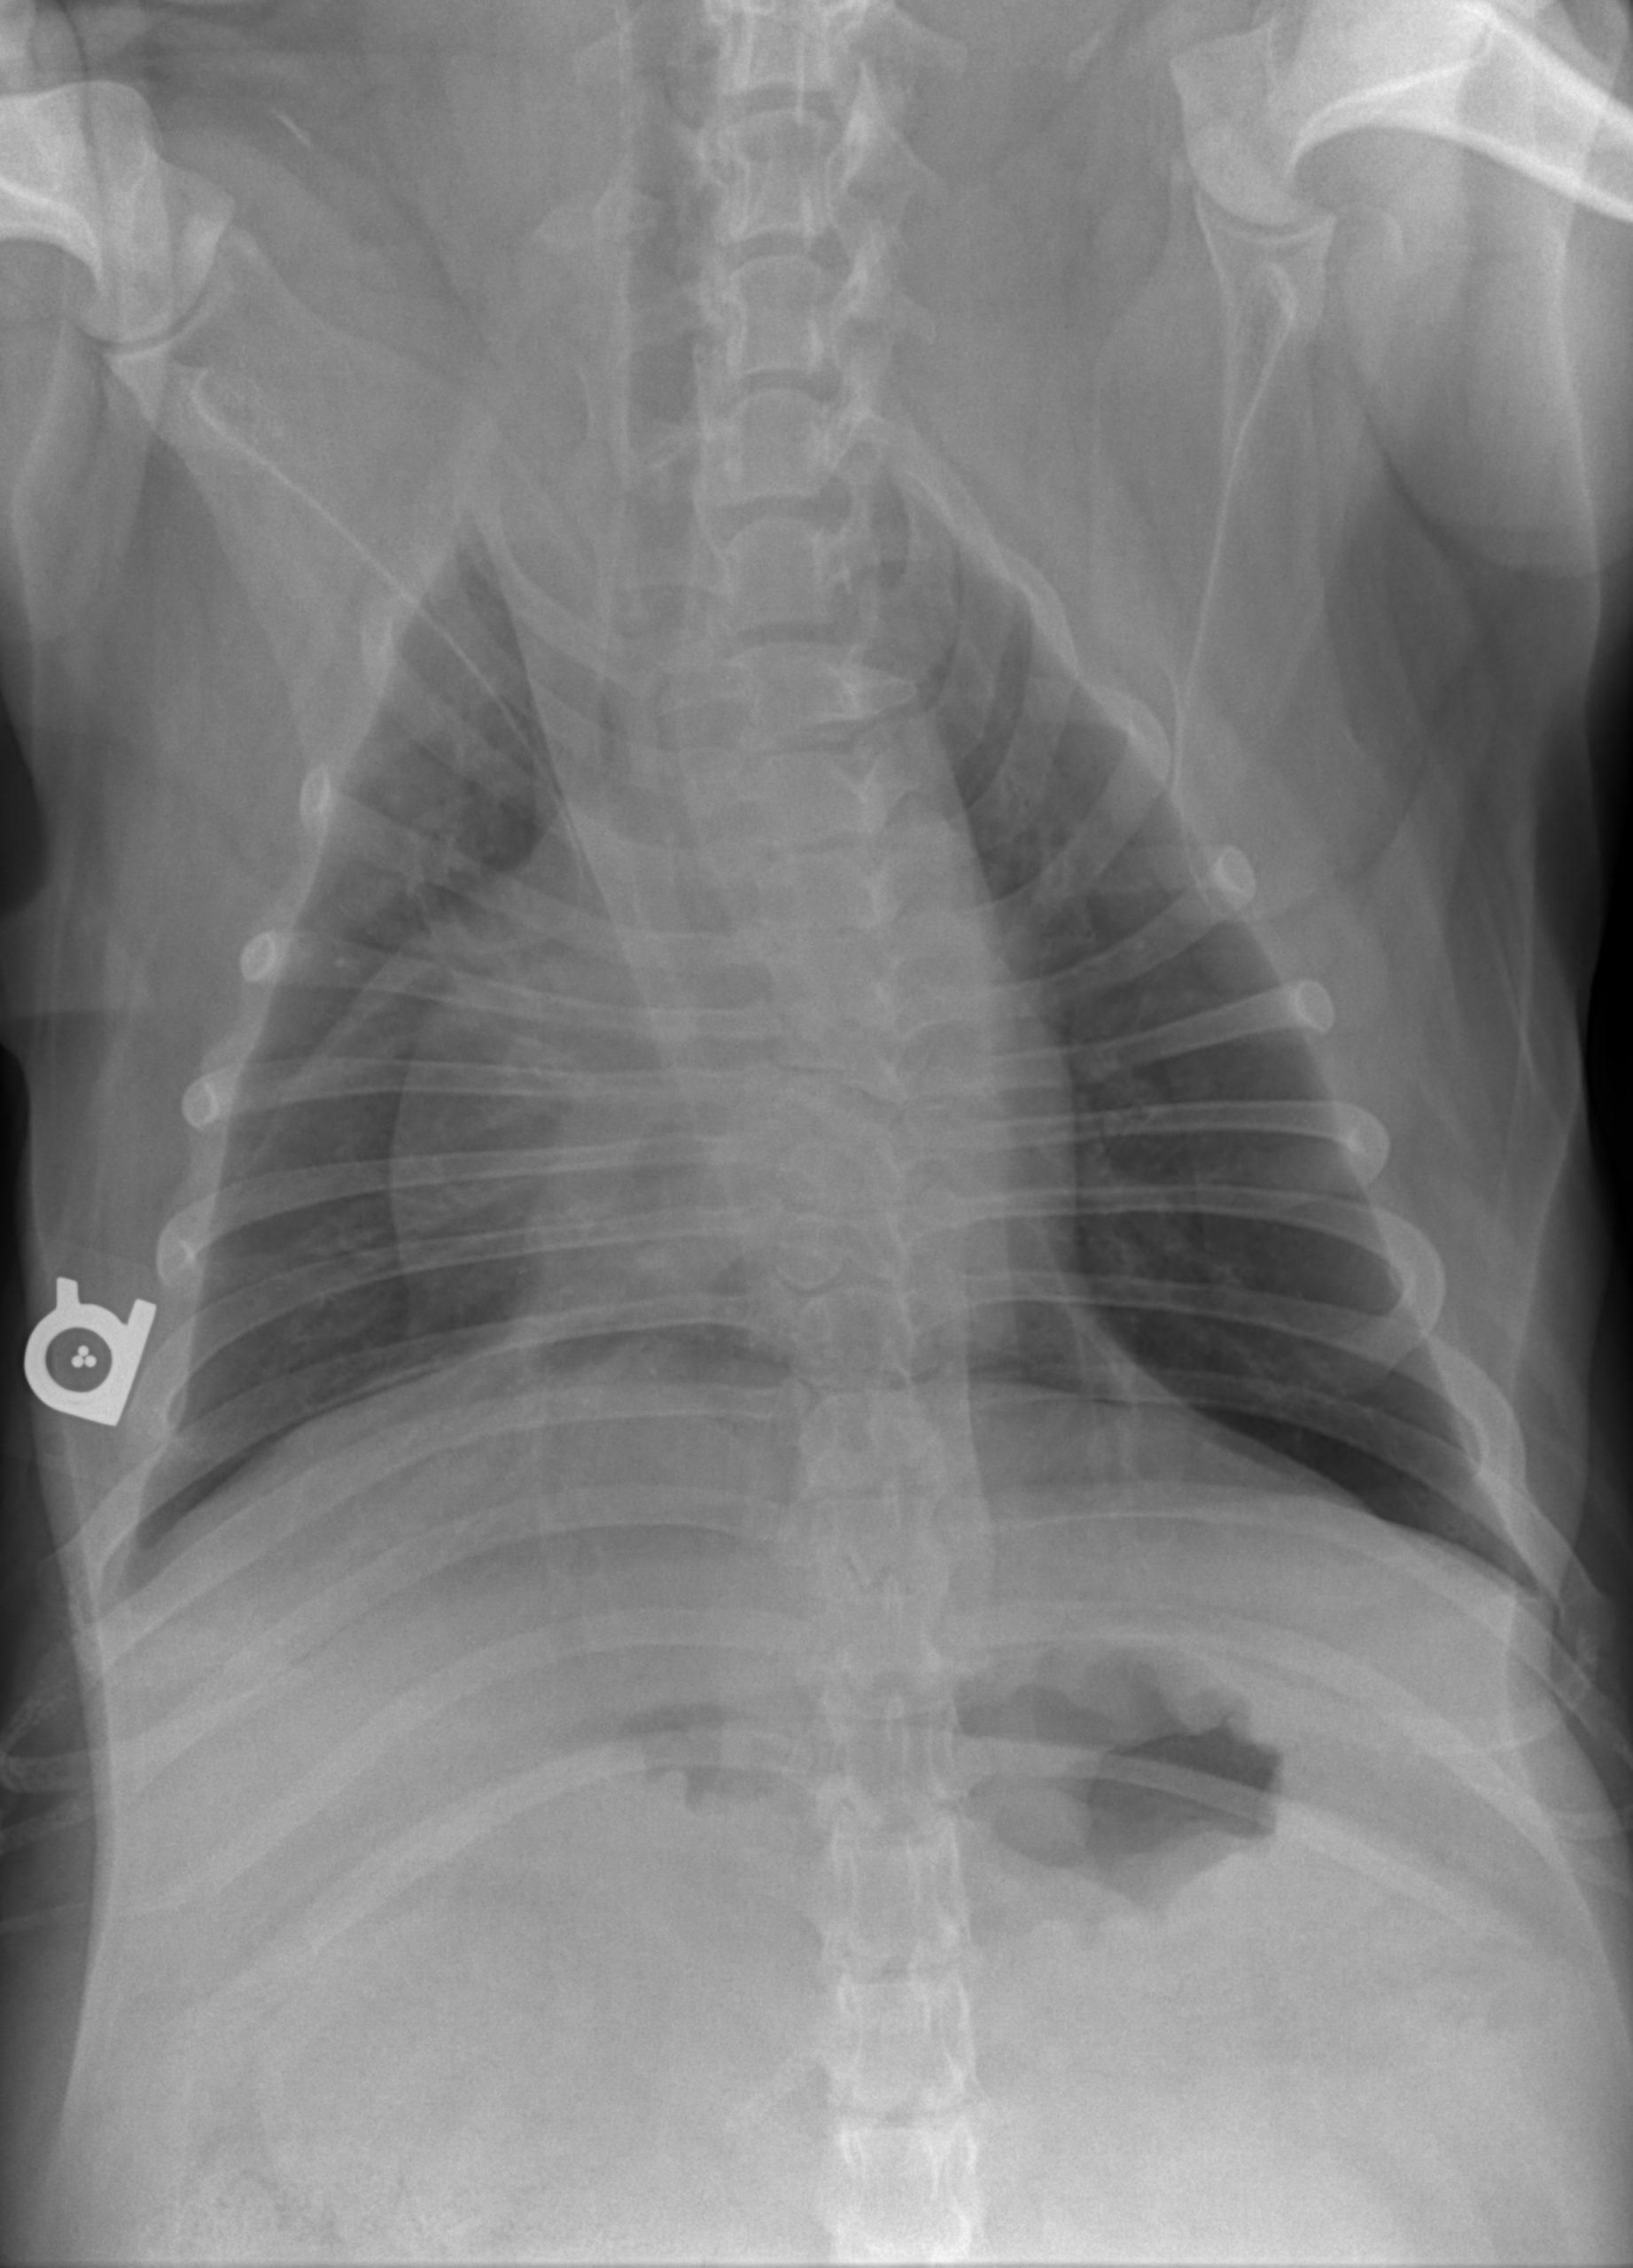

A 6-year-old intact male English Bulldog was presented for 2-3 days of intermittent vomiting and lethargy. Physical exam found the patient to be tachycardic with pale mucous membranes and a palpable mass in the abdomen. Serum biochemistry revealed elevated alkaline phosphatase, hypernatremia, and mild hypochloremia. On CBC, a decreased HCT in conjunction with a high MCV was noted, in addition to a neutrophilia, monocytosis and thrombocytopenia. No abnormalities were noted on thoracic radiographs. Abdominal radiographic findings revealed a loss of contrast in the cranial abdomen, with the possibility of a splenic mass. Radiographic Interpretation showed marked splenomegaly strongly suspected to be secondary to torsion, although accompanying infiltrative or neoplastic pathology could not be ruled out. The small volume of peritoneal effusion and inflammation was likely secondary to the splenic pathology. Thoracic radiographs showed mild microcardia and under perfused pulmonary vasculature in support of hypovolemia. Atypical intrathoracic fat distribution was considered to be incidental in this dog. This dog had multiple hemivertebrae.